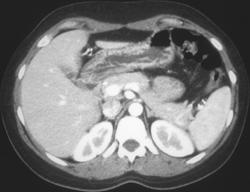

Gastric Adenocarcinoma